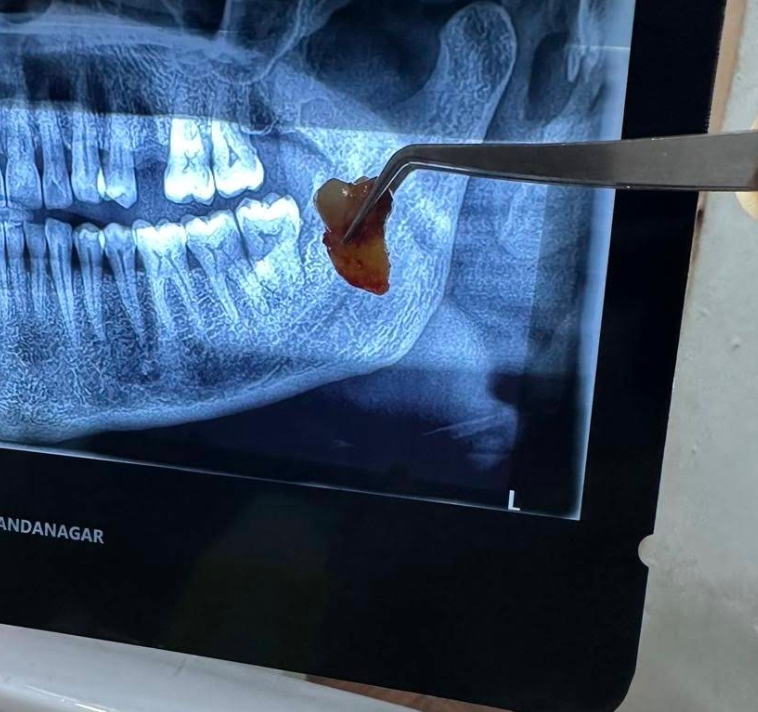

Safe and painless tooth extraction

Painless Extractions

Our extraction procedures are frequently highlighted by patients for being smooth and nearly painless. Dr. Mavia utilizes modern anesthesia techniques and a gentle approach to safely remove damaged or impacted teeth, ensuring a fast recovery process.

• Minimal discomfort approach

• Fast healing instructions